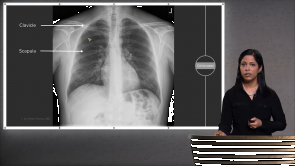

Clinical / USMLE Step 2